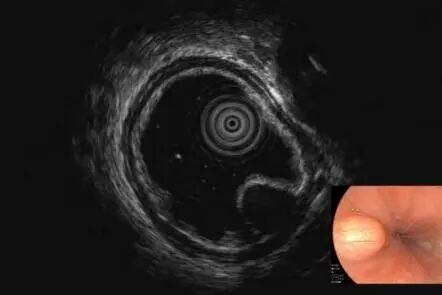

那么这个隆起是什么呢

我们进一步完善超声内镜检查后提升

胃壁固有肌层可见8.9X5.5mm的低回声

因间质瘤有恶变可能

考虑是间质瘤可能